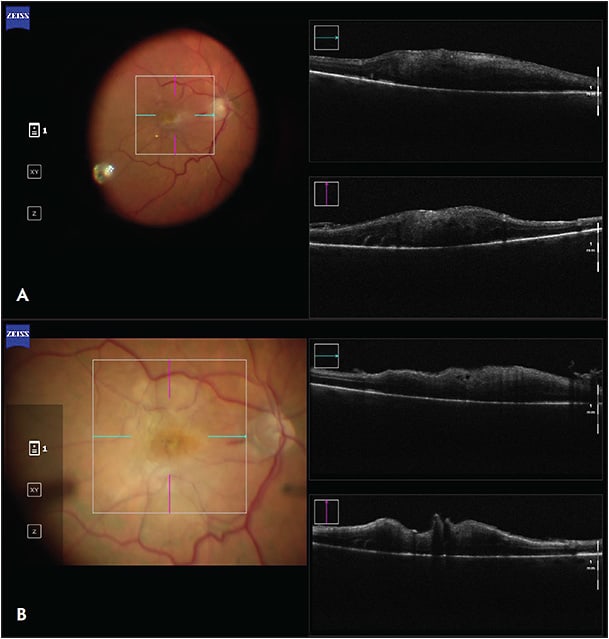

The utility of iOCT has been extensively described in macular surgery. Intraoperative OCT can reveal residual membranes or completion of the membrane peel (Figure 1), potentially avoiding incomplete treatment or unnecessary surgical maneuvers.10 Studies have shown that iOCT can identify occult residual membranes in 12% of cases and are useful in confirming a completed membrane peel in 9% of cases.4 The DISCOVER trial showed a discrepancy between what surgeons perceived and what was actually present during the surgery. In 40% of cases where the surgeon believed there were residual membranes, iOCT showed complete removal of the membrane.3 Other studies have demonstrated that iOCT-assisted macular hole surgery achieved a single-surgery success rate of 97.6%, which was comparable to outcomes without iOCT.10-12